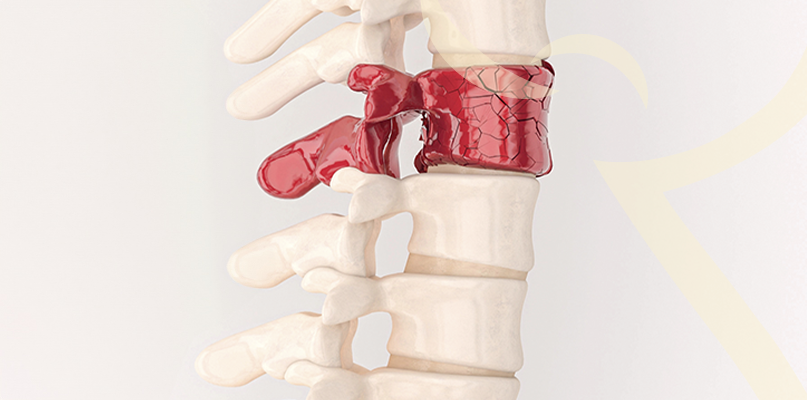

Fraturas da Coluna – diagnóstico e opções de tratamento

As fraturas vertebrais podem ocorrer por acidentes, quedas ou doenças como osteoporose. São condições que requerem diagnóstico rápido para evitar sequelas neurológicas.

Pode variar de imobilização e reabilitação a cirurgias minimamente invasivas (como vertebroplastia e cifoplastia), que promovem estabilização e alívio rápido da dor.